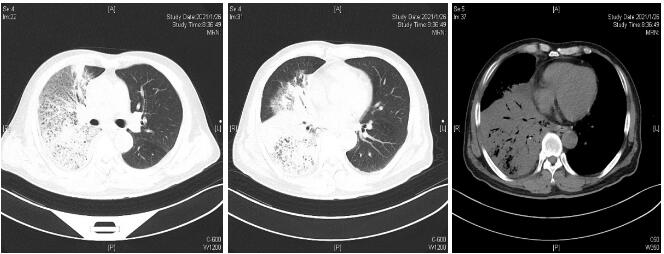

患者经过近1周治疗,临床症状较前好转,心衰纠正,炎症指标明显下降,于1月31日体温正常后转普通病房。感染方面美平降级为头孢派酮舒巴坦,继续多西环素治疗。2月2日外送标本DNA测序鉴定为Balneatrix alpica,即阿尔卑斯浴者菌。后续患者出现胸膜炎性胸痛,间断气促,复查肺部CT提示右侧胸腔积液量增多,给予穿刺引流,胸水外送经DNA鉴定报高山巴氏发菌,即Balneatrix alpica,至此患者感染的病原菌明确,考虑此菌为少见菌,对抗菌药物敏感性较高,后续抗生素方案降解为左氧氟沙星500 mg/d,经治疗3周后患者出院,后期随访追踪无不适。

| 图 2 2月1日复查胸部CT平扫 |